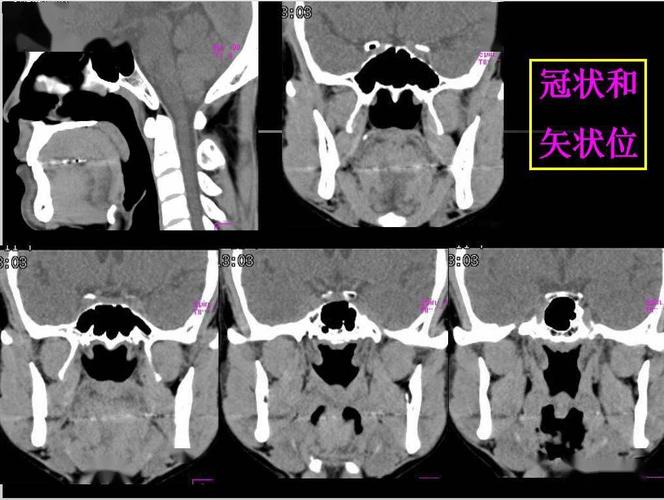

鼻咽ct解剖结构图

鼻咽ct解剖结构图,鼻咽部ct解剖图

鼻咽部的详细解剖(含各个孔道)

收藏必备 | 鼻咽部的ct详细解剖

鼻咽部ct解剖

鼻咽部断层解剖 详细标注